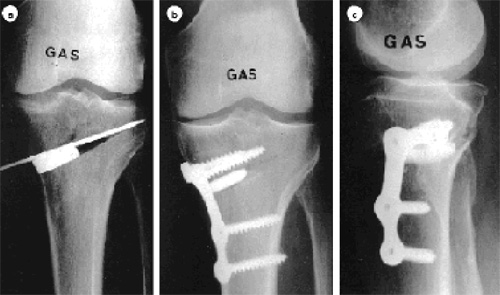

L’ostéotomie est réalisée en zone métaphysaire haute puis ensuite fixée provisoirement et la correction souhaitée est vérifiée sur l’écran.

Cette correction doit être suffisante afin de créer un valgus de 3 à 6°. L’ostéotomie est maintenue par une plaque vissée dont il existe plusieurs modèles sur le marché.

Plaque d’ostéotomie de valgisation

a) Contrôle radiologique per opératoire de l’ostéotomie et de l’ouverture, cale d’essai en place.

b) et c) Contrôle radiologique postopératoire.